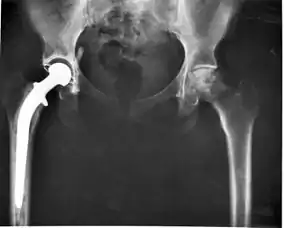

بعضی از کارکردها شاید ظریف باشند، مانند استفاده شدن در دریچهٔ قلب، یا شاید زیست فعال باشند با تعامل کاربردی بیشتر مثل هیدروکسی آپاتیت که ایمپلنتهای مفصل ران را پوشش میدهد. بیومدیکالها هم چنین هرروزه در سازههای دندانی، جراحی و دارورسانی استفاده میشوند. بهطور مثال یک سازهٔ آغشته به محصولات دارویی میتواند در یک بدن جای بگیرد، که اجازه میدهد این دارو مدت جذب بیشتری داشته باشد و در مدت زمان طولانی تری جذب شود.

این یک پدیدهٔ به شدت گسترده است؛ تمام شش طبقهبندی قلمروها شامل اعضایی میشوند که قادرند مواد معدنی تولید کنند و بیشتر از ۶۰ نوع مواد معدنی متفاوت در موجودات شناخته شدهاست. مثالها شامل سیلیکاتها در جلبکها و دیاتومها، کربناتها در بی مهرگان و کلسیم فسفاتها و کربناتها در مهره داران است.[4][5][6] این مواد طبیعی معمولاً ساختار ظاهری را شکل میبخشند، مانند صدفها و استخوانها در پرندگان و پستانداران. موجودات زنده بیش از ۵۵۰ میلیون سال است که اسکلت معدنی تشکیل میدهند. مثالهای دیگر مانند کانسار یا تهنشینهای مس، طلا و آهن است که شامل باکتری میشود. مواد معدنی بیولوژیک غالباً استفادههای خاصی مانند سنسورهای مغناطیسی در باکتریهای مغناطیسی دارند، دستگاههای احساس جاذبه و ذخیرهٔ آهن و تحرک. انتخاب بیومواد تمام موادی که در پزشکی برای کاشتن یا مصرف به کار می روند، از جنس فلزات، پلیمرها، سرامیک ها و کامپوزیت ها و یا ترکیبی از مواد مذکور می باشند. جایگزینی بافت با مواد مصنوعی از طریق انتخاب ماده ای که خواص فیزیکی-مکانیکی آن بسیار شبیه و نزدیک به بافت طبیعی است، به انجام می رسد.برای کاربردهایی در رابطه با بافت نرم (پوست، زردپی، بند یا رباط، پستان، چشم، سیستم عضلانی و صورت) بسپارهای طبیعی یا مصنوعی برای جایگزینی بافت صدمه دیده استفاده میشود.فلزات، سرامیک ها و کامپوزیت ها به طور گستردهای برای جایگزینی یا تقویت و مستحکم سازی دندان و استخوان به کار می رود. ضریب کشسانی و استحکام بافت های نرم معمولا کمتر از 100 مگا پاسکال است؛ بنابراین پلیمرها با داشتن استحکام مشابه و استحکام کشسانی کمی بالاتر متداولترین ماده برای جایگزینی این نوع بافت ها به شمار میآیند. برعکس استخوان دارای استحکام کششی بالاتری است و ضریب کشسانی آن خیلی بیشتر از ضریب کشسانی بافت نرم میباشد.از آنجا که پلیمرها دارای ضریب کشسانی حدود 10 گیگا پاسکال نمیباشند آلیاژهای فلزی، سرامیک ها و کامپوزیت های تقویت شده با رشته برای جایگزینی استخوان مصرف می شوند.

نقطهٔ ابهام این جمله پیشرفتهای مداوم نگرشی در چگونگی اثر متقابل زیست مادهها با بدن انسان رو منعکس میکند و در نهایت اینکه این تقابلها چگونه موفقیت بالینی تجهیزات پزشکی را معلوم میکنند مثل دستگاه تنظیمکنندهٔ ضربان قلب و دستگاه جایگزینی مفصل ران.